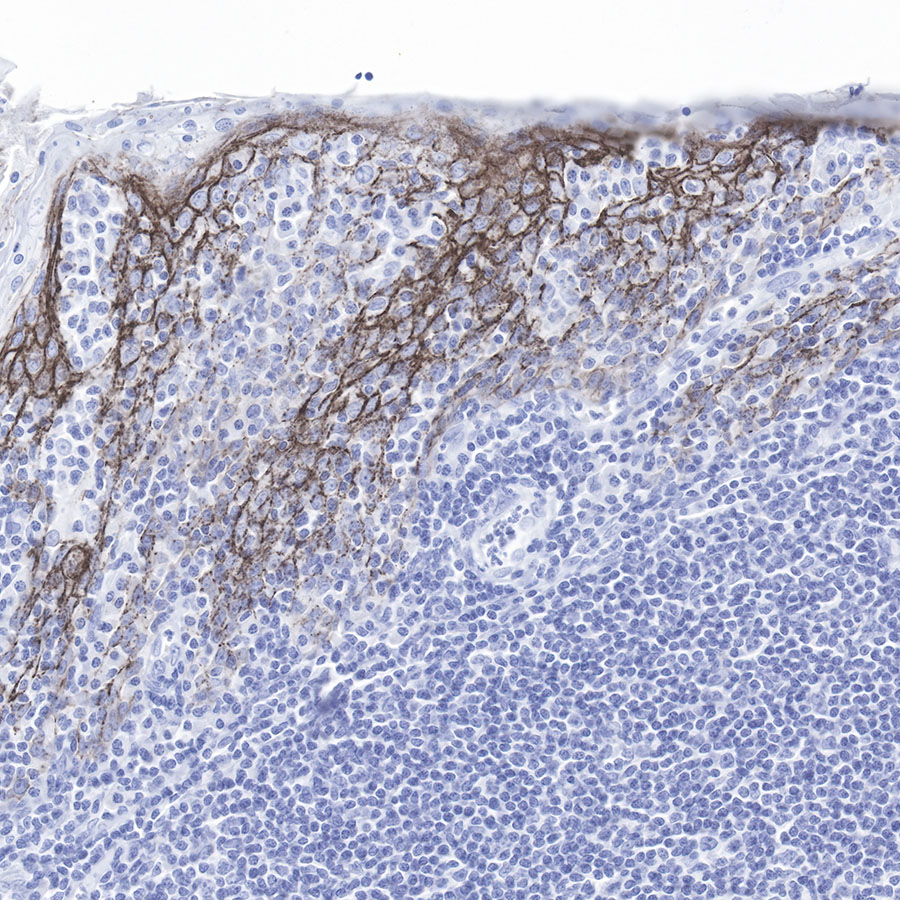

IHC shows positive staining in paraffin-embedded human tonsil.

Anti-Claudin-1 antibody was used at 1/500 dilution, followed by a Goat Anti-Rabbit IgG H&L (HRP) ready to use. Counterstained with hematoxylin.

Heat mediated antigen retrieval with Tris/EDTA buffer pH9.0 was performed before commencing with IHC staining protocol.